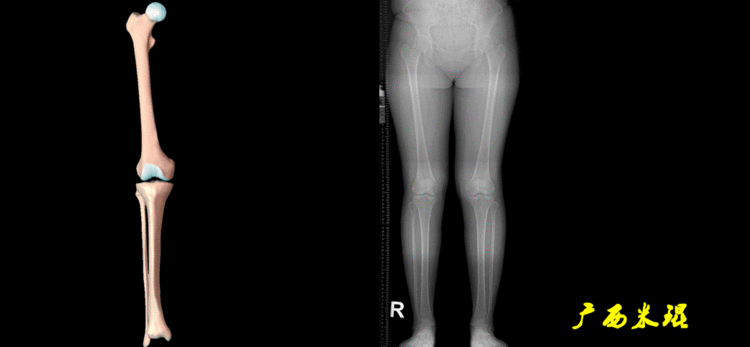

最常见的下肢畸形发生于冠状面,即膝内外翻畸形,冠状面的对线异常通过应用“对线异常检验”进行分析,机械轴的偏移(MAD)表现为对线异常。

膝内翻是指下肢力线通过膝关节中心点内侧,距中点2mm以上,偏内超过15mm为显著膝内翻。膝外翻是指下肢力线通过膝关节中心点外侧,距中点2mm以上,偏外超过10mm为显著膝外翻。

2、判断畸形的部位画出下肢全长片中的机械轴和力线轴,确定畸形来自股骨、胫骨还是关节内。首先我们确认股骨机械轴及mLDFA,超出范围为股骨畸形;然后我们确认胫骨机械轴及MPTA,超出范围为胫骨畸形;最后我们确认关节线的汇聚关系JLCA,超出范围为关节内畸形。